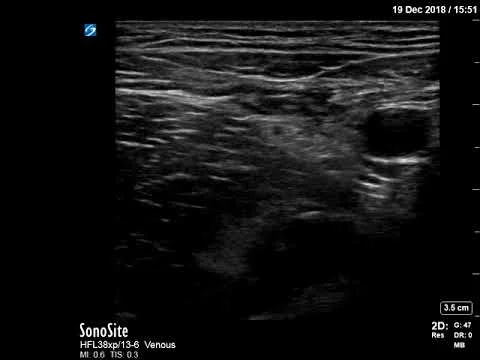

Distal radius fracture